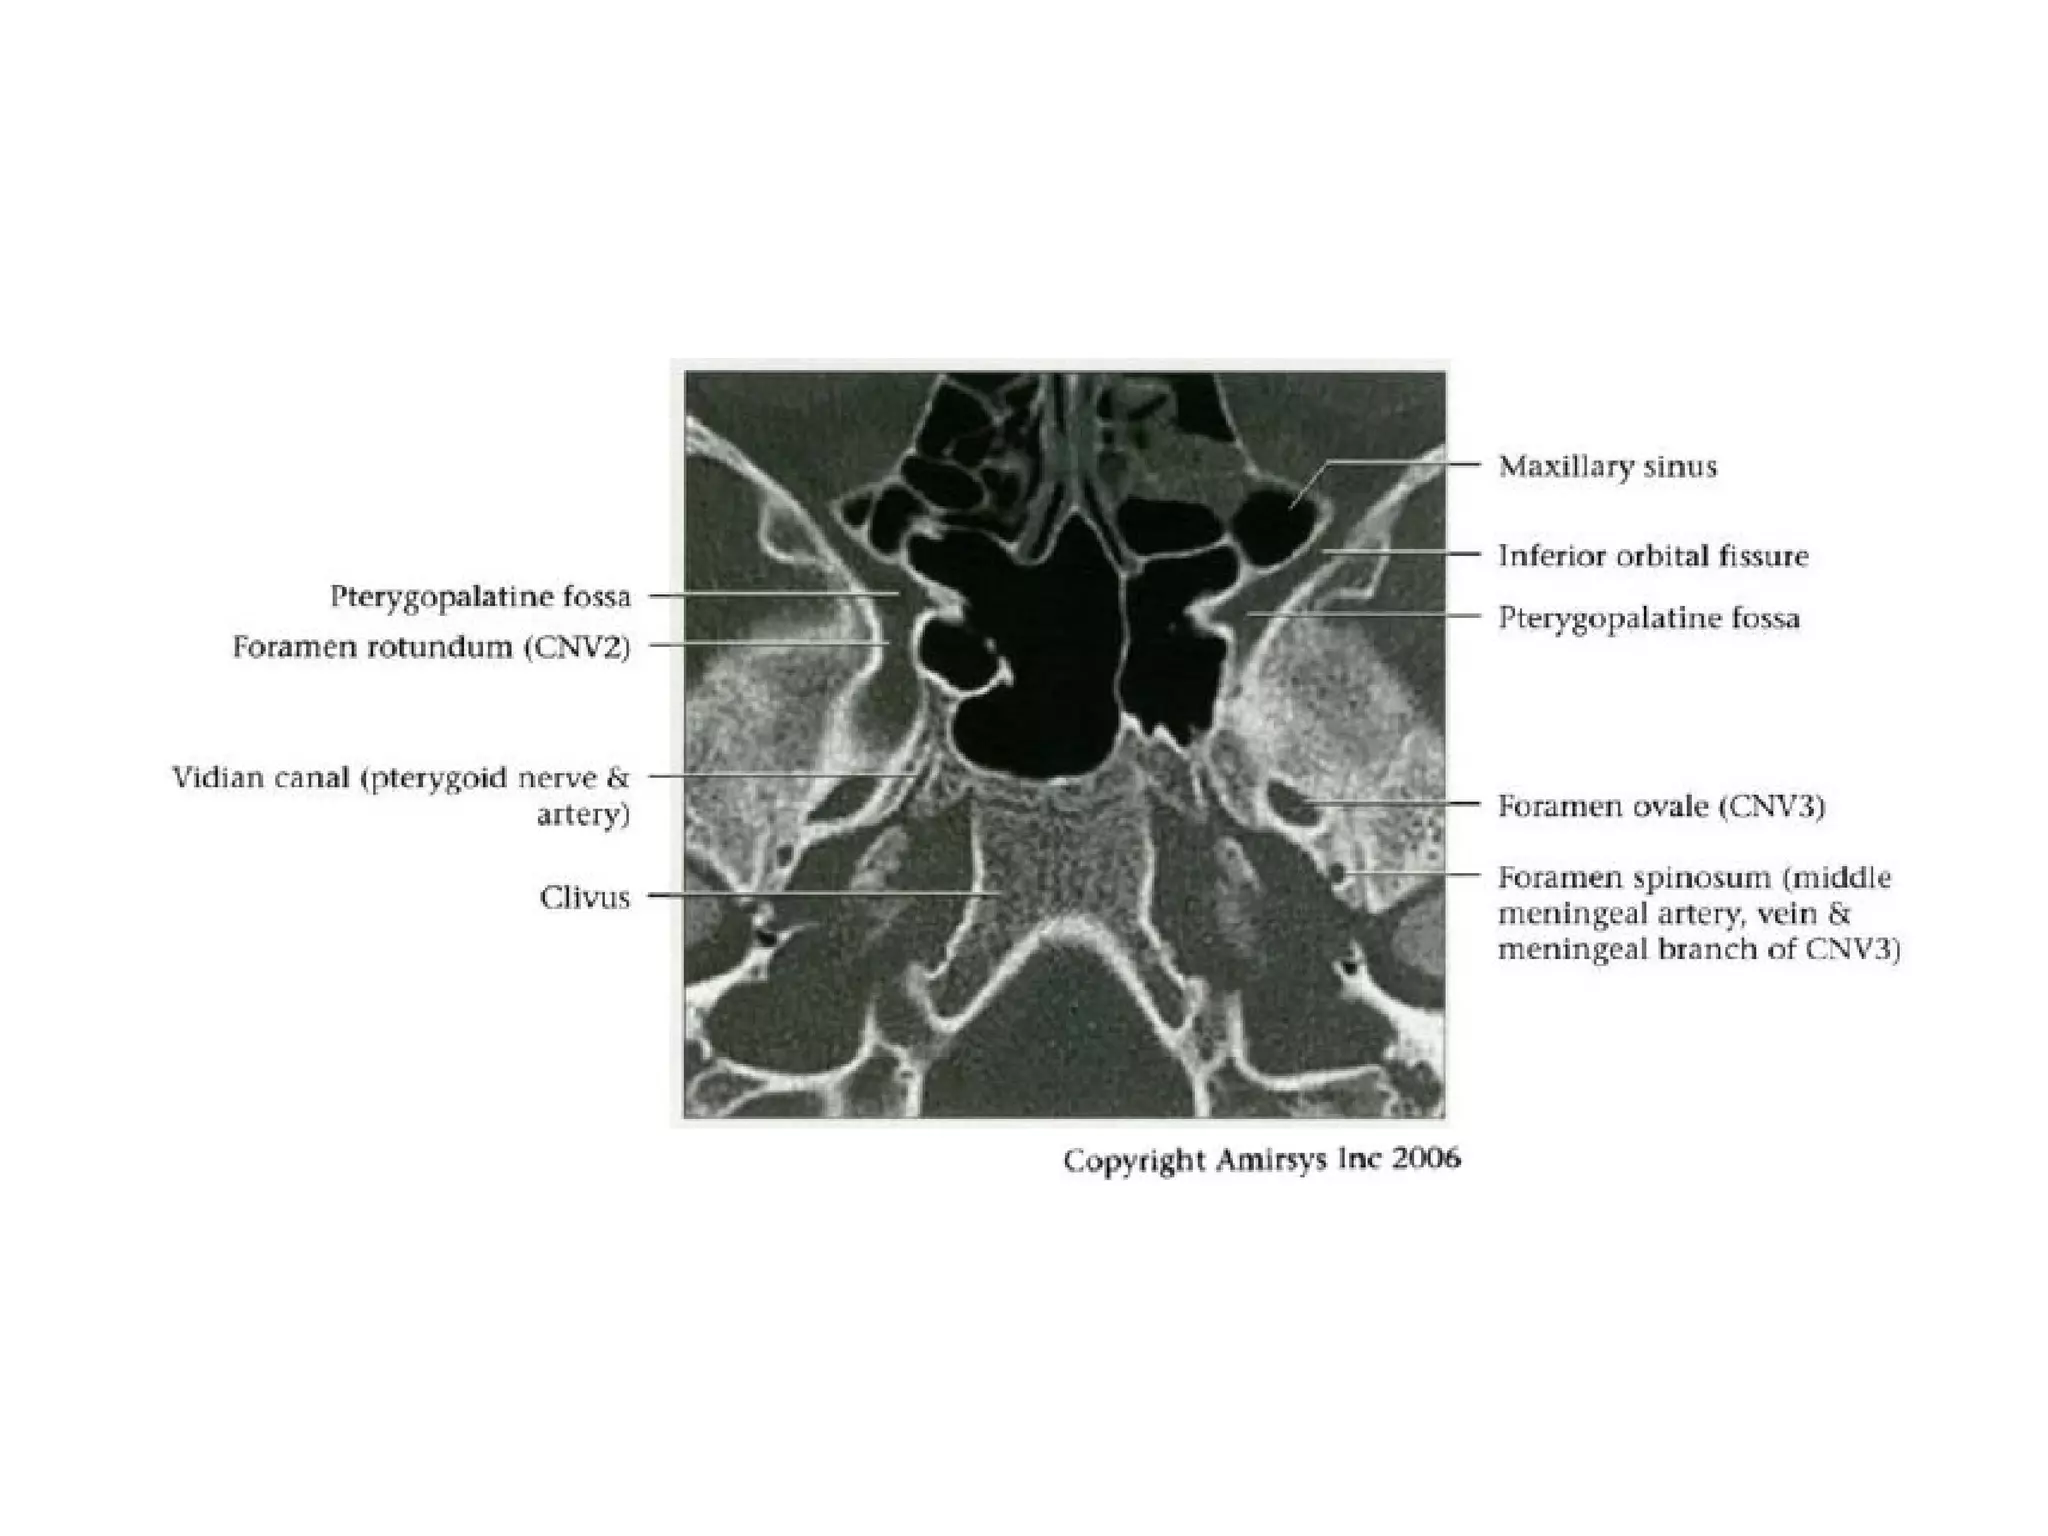

Divisions (Post-Ganglionic) of CNS

Maxillary nerve (CNV2)

• Courses in cavernous sinus lateral wall

below CNV 1

• Exits skull through foramen rotundum

• Traverses roof of pterygopalatine fossa

• Continues as infraorbital nerve in floor of

orbit

• Exits orbit through infraorbital foramen

- Sensory to cheek and upper teeth

Mandibular nerve (CNV3)

• Does not pass through cavernous sinus

• Exits directly from Meckel cave, passing inferiorly

through foramen ovaIe into masticator space

• Carries both motor and sensory fibers

- Motor root bypasses TG, joins V3 as it exits through

foramen ovale

- Divides into masticator (muscles of mastication) and

mylohyoid nerves (mylohyoid and anterior belly of

digastric muscles)

- Masticator nerve take off just below skull base

- Mylohyoid nerve take off at mandibular foramen

• Main sensory branches include inferior alveolar, lingual

and auriculotemporal nerves